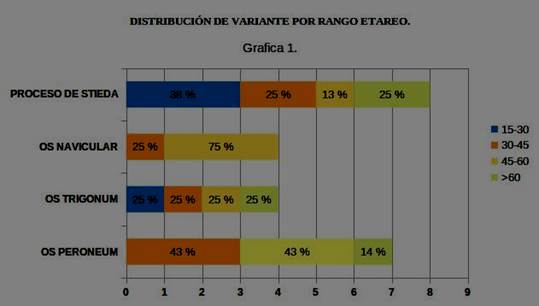

El 65,22% de los hallazgos se ubicaron en pacientes entre 30 y 60 años. (Gráfica 1).